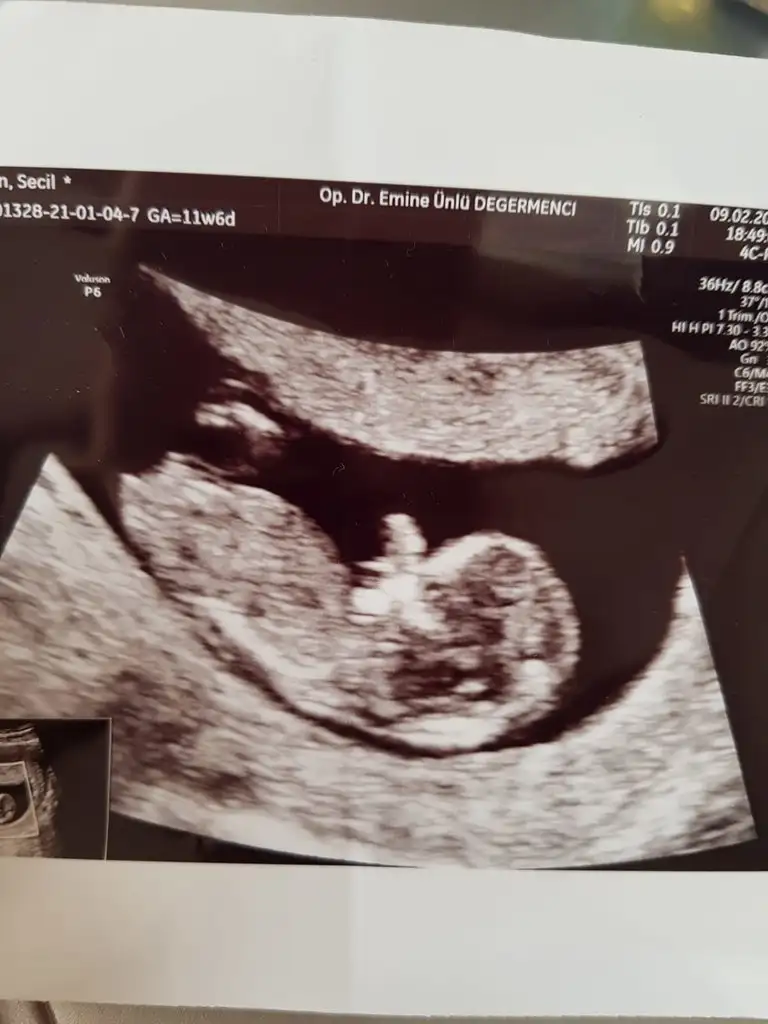

Arkadaşımın bebeğinin cinsiyetini de tahmin edermisiniz😊